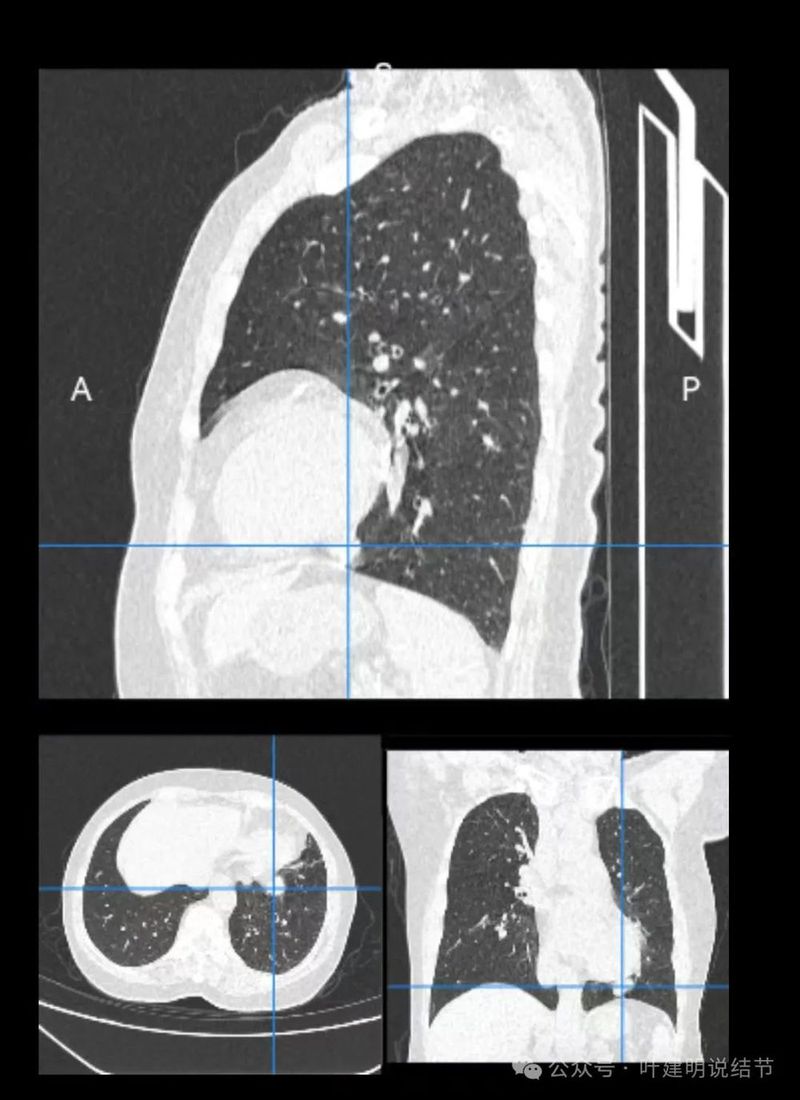

上图层面相对最大,感觉鼓鼓的。

边界与轮廓清。

上图显得膨胀感欠了点,但分叶与表面不平是明显的。

边比较为平直,密度仍实。

感觉两处不同的中心,如果连续层面看,应该是病灶不平的关系,与膈肌间仍有间隙,密度是实性的。

边缘区域的样子。

纵隔窗见病灶实性密度,与膈肌间有低密度线状间隙。

病灶密度稍不均。

较为边缘部分的纵隔窗样子。